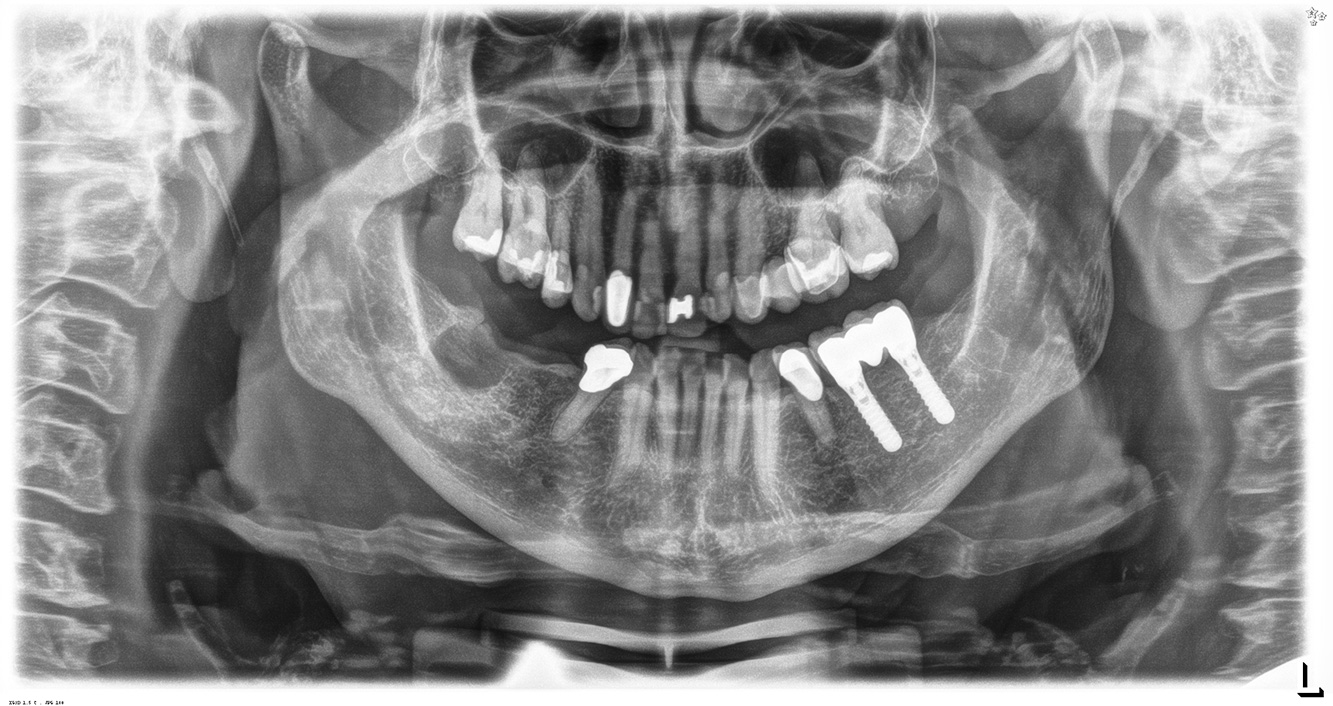

In the medical history, the 55-year-old patient states that he has no systemic disease and is not taking any medication. The patient’s lifestyle is similarly unremarkable. The patient has a few tooth restorations and two implants (2nd and 4th quadrants). On the basis of current findings, gingivitis is identified in an otherwise stable periodontal condition on the reduced periodontium (stage III, grade A). more

The healthy patient with pre-existing periodontal disease & peri-implantitis

The healthy patient with early periodontal disease

The 68-year-old patient has no general health conditions and is not taking any medication that may be relevant to her oral health, and her lifestyle does not pose any particular risk. The patient has two dental implants (3rd quadrant, for five years) and a previous case of periodontal disease (stage IV, grade B periodontitis) with tooth loss. Currently the periodontal conditions are stable. However, periodontitis significantly increases the biological complications of implantations and there is a risk of implant loss (21). Four recommendations can be determined for the prophylaxis session. more